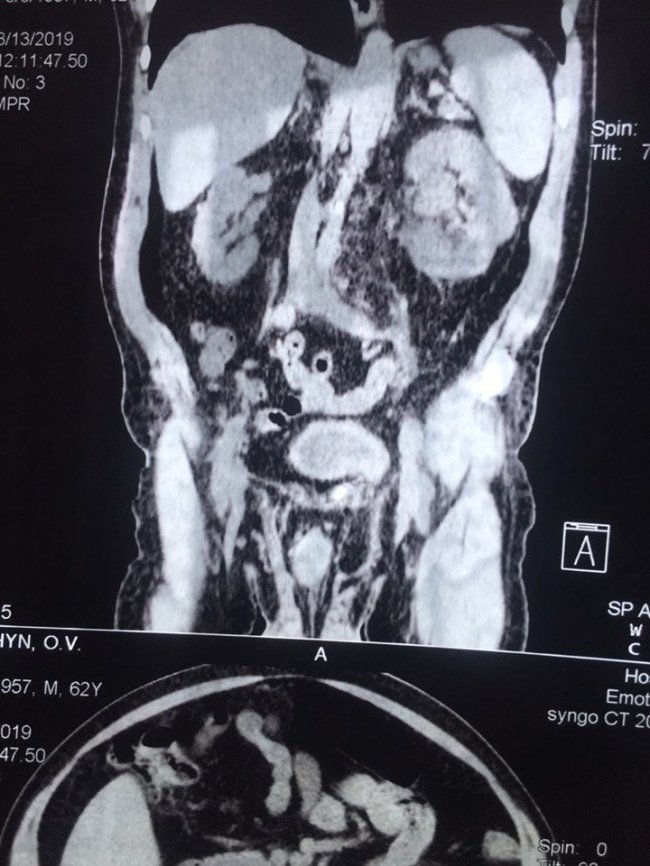

Волинянину провели три операції під час одного наркозу. ФОТО

Минулого тижня в урологічному відділенні нововолинські лікарі успішно провели три операції на різних органах під час одного наркозу.

Так, одночасно видалили 2 камені з лівого сечоводу, 4 камені з сечового міхура та зробили пластику лівобічної пахової кили.

Зауважимо, операційна бригада у складі: Шипелик О. В., Винницький І. В., Гідзінський А. М, Новосад І. В.

Симультанні операції - втручання, коли під час однієї операції виконують декілька оперативних прийомів на різних органах.